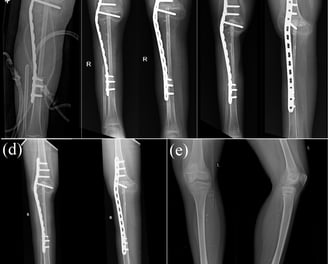

Combination-type periprosthetic tibial fracture: Felix type (II+IV)A

Tibial periprosthetic fractures are rare but present a complicated problem for orthopaedic surgeons. Literature in relation to combination-type periprosthetic fractures is extremely scarce, and there is limited guidance available on its treatment. We report the case of a woman in her 60s, whose radiographs revealed a periprosthetic fracture of the tibia, which was a Felix type (II+IV)A fracture. Our demonstrated treatment of a Felix type II+IV periprosthetic fracture could be a viable treatment option for such fractures.